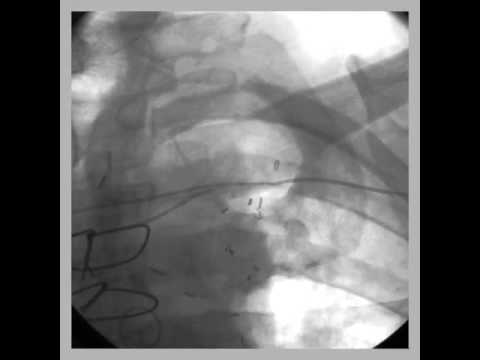

Video 53.1

Video 53.1 Fluoroscopy showing a 4-lead implantable defibrillator system for multisite pacing in the right atrium and biventricular pacing and defibrillation back up in a 40-year-old patient with refractory congestive heart failure class 3, dilated cardiomyopathy, and refractory persistent atrial fibrillation after pulmonary vein ablation and antiarrhythmic drug therapy.